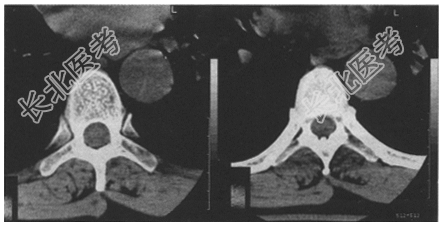

- [材料题] 患者,男,44岁。突发胸背部疼痛,伴双下肢无力10分钟。既往有高血压病史。查体:T₁₀~T₁₂棘突处压痛,双下肢肌力0级,左下肢感觉减退。胸部X线平片未见异常。胸椎CT周围平扫图像如下。

- 简答题1、请问你认为该患者进一步的诊治方案是什么?